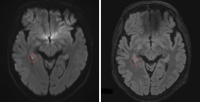

Wie spezifisch sind die klinischen Kriterien für die transiente globale Amnesie? // How specific are the clinical criteria for transient global amnesia?